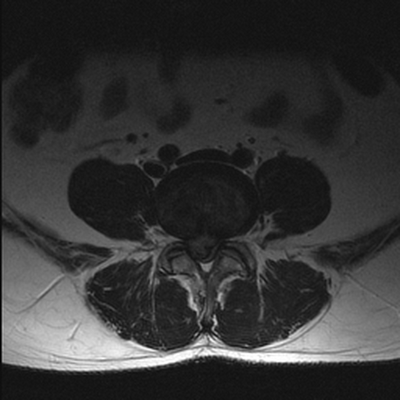

МРТ: межпозвонковая грыжа диска L4-5 (аксиальная проекция, Т2 ВИ)